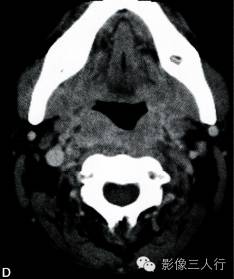

A~C.CT平扫横断面;D~F. CT增强横断面;G. HE×40

双侧甲状腺、颌下腺及咽淋巴环见多发结节融合状软组织影,边界不清,可见包膜,病灶密度欠均匀,内可见线样分隔,未见明显坏死及钙化,双颈各区可见大小不等的淋巴结,边界欠清,密度较均匀(图A~C)。增强横断面(图D~F)扫描双侧甲状腺、颌下腺及咽淋巴环病灶包膜及分隔可见明显强化,双颈淋巴结可见较明显强化。